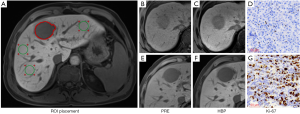

Quantitative analysis

All quantitative measurements of SI were performed on the picture archiving and communications system (PACS) by two abdominal radiologists (Likun Cao and Yi Wei with 4 and 10 years of experience in abdominal MRI). The observers were blinded to the other imaging results, any clinical information, and the final pathological diagnoses, and the first radiologist measured the SI again after one month. For liver parenchyma, three circle regions of interest (ROIs) with 3 cm2 area were respectively placed on the left lobe, right lobe anterior and posterior segments, avoiding major vessels, tumor, and bile ducts. For HCC lesion, three freehand ROIs with size ranging from 1.06 to 88.24 cm2 were drawn along the tumor margin at or next the level of the largest diameter of the tumor, excluding vessels and necrotic areas. The average SI of liver parenchyma and the tumor was recorded as L0 and T0 based on PRE, and as L20 and T20 based on HBP, accordingly. The quantitative parameters were then calculated as the following formulas.

- Relative tumor enhancement (RTE):

- Tumor to liver contrast ratio (TLR):

- Tumor enhancement index (TEI):

- Relative enhancement ratio (RER):

The representative images with ROI placement and quantitative measurements were demonstrated in Figure 2.